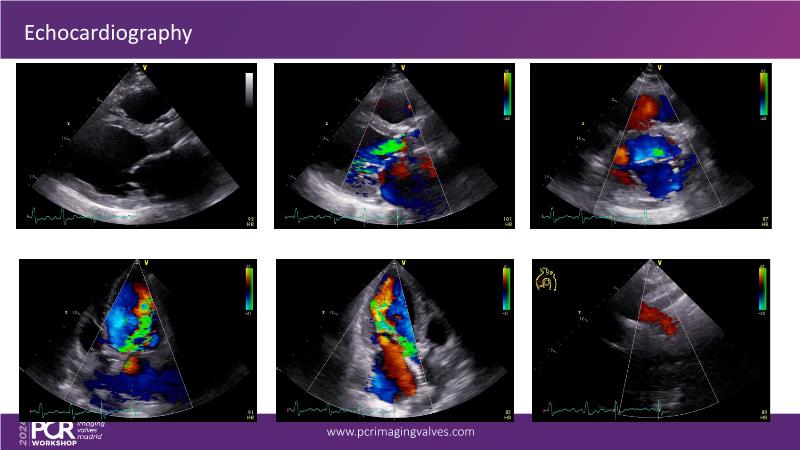

Explore cutting-edge transcatheter valve interventions for mitral and aortic valve disorders, including valve-in-valve procedures and management strategies for paravalvular leakages, and learn about diagnosing and treating mitral annular calcification and transcatheter options in infective endocarditis.

- To manage patients with mixed and multiple valvular heart disease: from risk stratification to therapeutic decision-making

- To get tips and tricks for guidance of transcatheter intervention